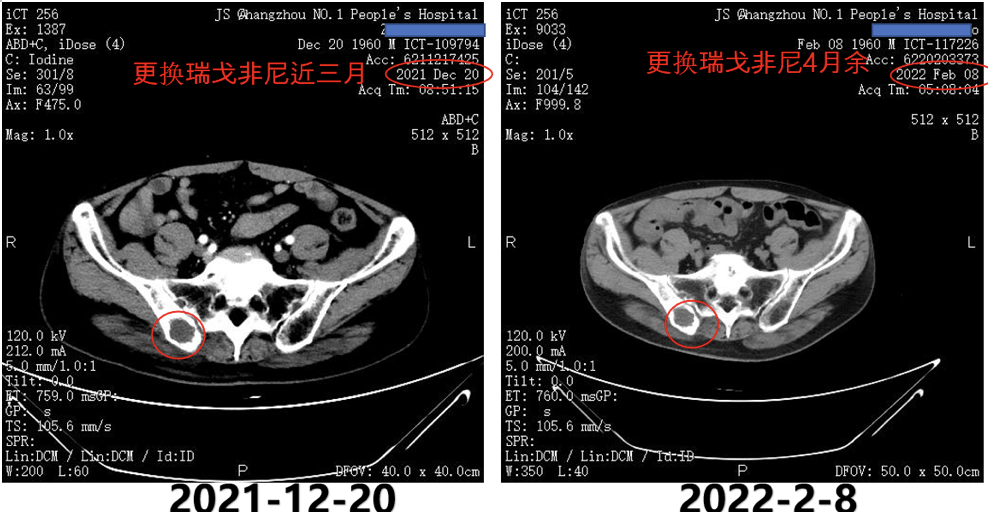

2021年3月8日复查AFP为>1210ng/ml;2021年3月8日复查CT提示,双肺转移双侧肾上腺转移;左侧肾上腺较前变小,但右侧肾上腺明显增大;右侧髂骨转移(图5)。

图5.2021年3月8日复查CT